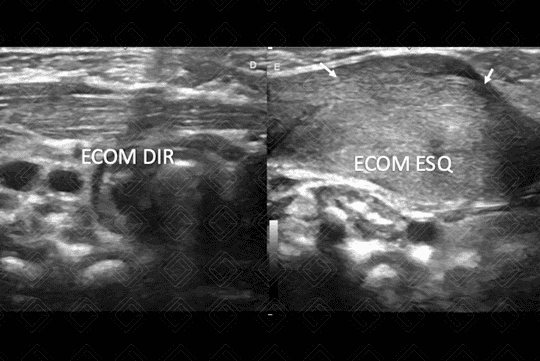

Texto alternativo para a imagem Créditos: Dra Elazir Mota - Rio de Janeiro/RJ

Descrição da lesão: Torcicolo congênito. Ultrassonografia da região cervical para avaliação de neonato com "massa" palpável ao exame físico na região cervical anterior esquerda. Durante a ectoscopia, observa-se a cabeça do paciente inclinada para o lado da lesão. A ultrassonografia revelou aumento da espessura e ecogenicidade das fibras musculares do esternocleidomastoideo (ECOM) à esquerda- setas brancas. Foi realizada análise comparativa: a direita, observamos ECOM normal e, à esquerda, sua espessura e ecogenicidade aumentadas

Exames de imagem: Ultrassonografia (US) cervical é o grande exame a ser solicitado. Deve ser realizado por radiologista pediátrico experiente para o adequado posicionamento do paciente. Na US evidencia-se aumento da espessura e ecogenicidade das fibras musculares do esternocleidomastoideo (ECOM).